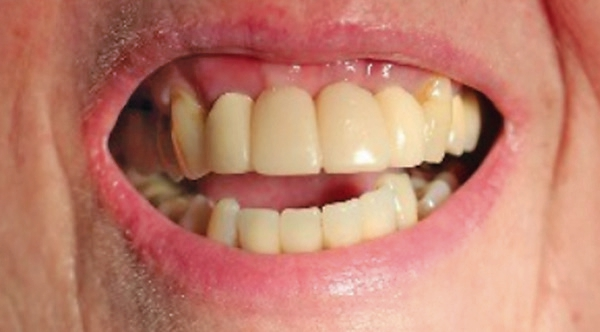

Das post-operative Follow-up zeigte eine komplikationslose Heilung. Sechs Monate nach der Operation wurde das Re-entry durchgeführt und Gingiva-Former eingesetzt (Abb. 19). Die provisorische Brücke zeigte ästhetische Ergebnisse bereits sechs Monate nach Operation (Abb. 20). Das Röntgenbild zeigte stabile Knochenverhältnisse (Abb. 21).